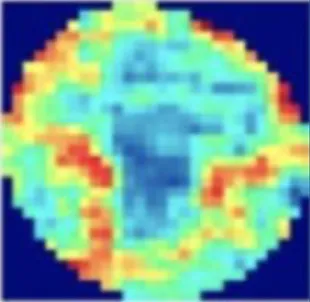

Parametric mapping

Parametric mapping techniques (T1, T2, T2* and ECV mapping) traditionally involve mathematical fitting of different cardiac images acquired with different acquisition parameters. Appropriate alignment (registration) is essential, as unaccounted cardiac or respiration motion will reduce image quality and parameter quantification accuracy. AI has been applied to mapping techniques such as T1 to improve motion correction. For example, CNN approaches like MOCOnet, trained on over 1,500 UK Biobank T1 maps with artificially generated motion artefacts, achieved rapid (<1 s) and robust suppression of artefacts in native T1 maps from 200 test subjects, outperforming traditional methods in both visual quality and reproducibility (31). More recently, deep learning–based end-to-end reconstruction frameworks have integrated motion estimation and correction into a single pipeline for 3D whole-heart T1/T2 mapping, reducing reconstruction times from hours to seconds while preserving quantitative accuracy (11). These techniques demonstrate how deep learning can enhance motion correction, enabling more rapid and accurate mapping quantification. Commonly motion correction is applied in-line for clinical scans, and therefore work is needed for deployment across scanners and vendors.